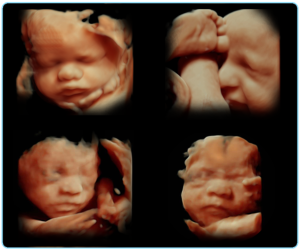

Ecografías 3D y 4D video

Ecografías 3D y 4D video Una de las innovaciones más recientes y de mayor impacto en el campo del diagnóstico prenatal ha sido la incorporación de

Ecografía 3D y 4D

constituye la última novedad en servicios de ecografías. Nos permite obtener impresionantes imágenes con un extraordinario realismo. Las ecografías en alta resolución brindan una claridad de imagen con un realismo único. Esta innovadora herramienta permite la posibilidad de integrar el volumen (3D) con una fuente de luz que ayuda a aumentar la percepción de profundidad, revelar detalles ocultos y proporcionar un conocimiento más profundo de la anatomía de su bebé y en tiempo real (4D)